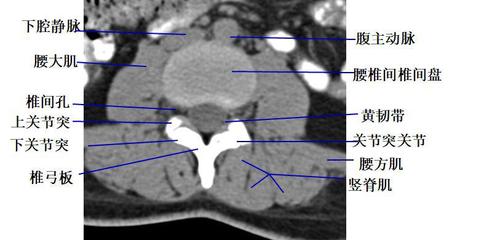

经腰椎椎弓根的横断层面(ct ) 1.